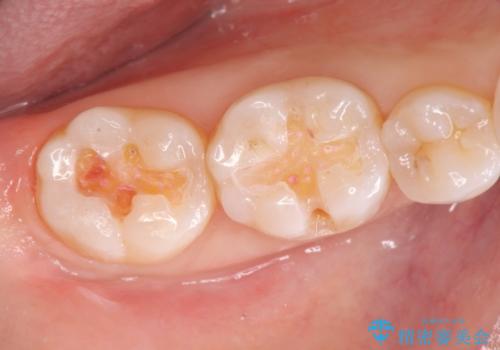

銀歯の下には初期の虫歯も見られたので、除去後精密なシリコン印象を行いセラミックインレーを製作しました。

審美性を回復し、虫歯も予防のできる精密なセラミックインレーを装着することができました。